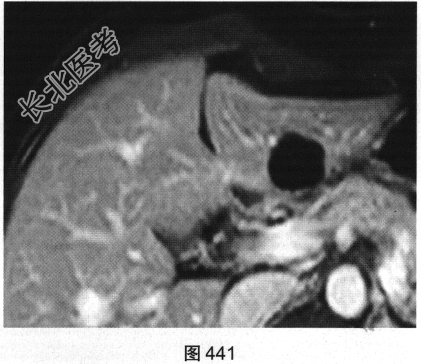

- 多项选择题3.[提示]增强扫描后的病变见图440、图441。此时考虑的诊断为( )

A、肝细胞癌

B、胆管细胞癌

C、肝囊肿

D、肝腺瘤

E、肝脓肿

F、肝海绵状血管瘤

关注下方微信公众号,搜题查看答案